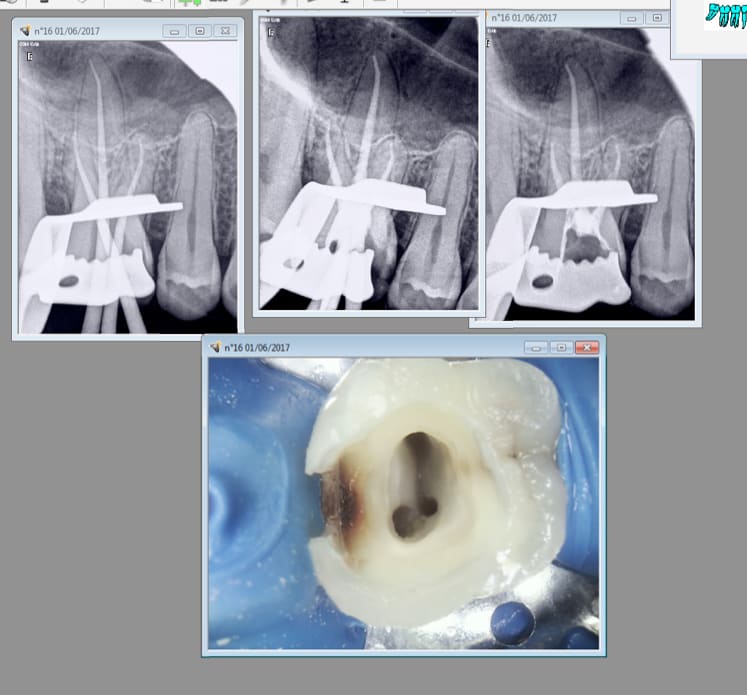

Localisateur dentjoy mini et CA chinetoc . Bon j'ai fini au R25 mais je pense que j'aurais pu finir au protaper gold.

( séquence SX et S1 gold puis R 25)

T'emmerdes pas à dépenser une fortune.

01/06/2017 à 13h06

On gagne à tous les coups. Et en 45 mn max. -)